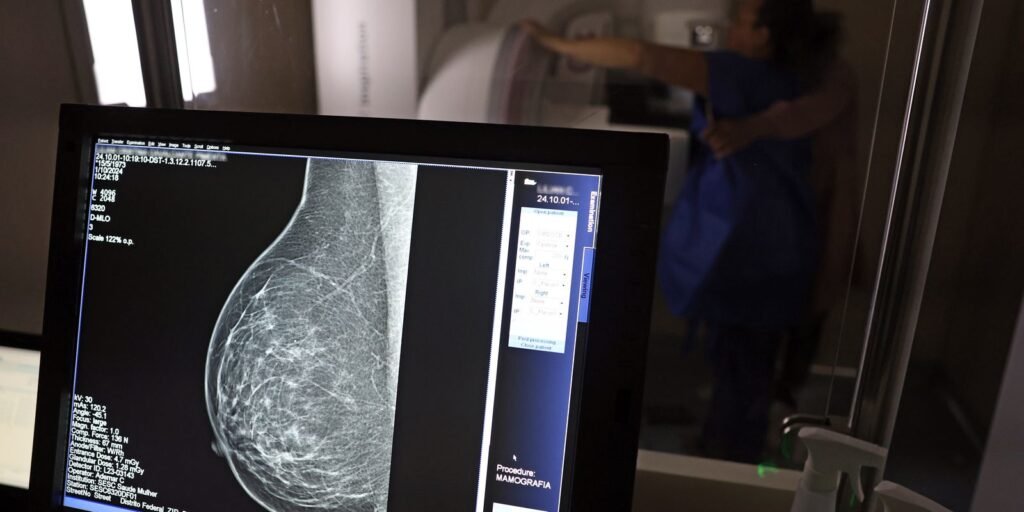

O Ministério da Saúde passou a recomendar o acesso a mamografia, via Sistema Único de Saúde (SUS), para mulheres de 40 a 49 anos – mesmo que não haja sinais ou sintomas de câncer de mama. De acordo com a pasta, a faixa etária concentra 23% dos casos da doença, e a detecção precoce aumenta as chances de cura.![]()

Até então, a orientação era que o exame fosse feito a partir dos 50 anos.

A medida faz parte de um conjunto de ações anunciadas nesta terça-feira (23) voltado para a melhoria do diagnóstico e da assistência. A recomendação para mulheres a partir dos 40 anos é que o exame seja feito sob demanda, em decisão conjunta com o profissional de saúde.

As mamografias via SUS em pacientes com menos de 50 anos, de acordo com a pasta, representam 30% do total, o equivalente a mais de 1 milhão apenas no ano de 2024.

Outra medida anunciada é a ampliação da faixa etária para o rastreamento ativo – quando a mamografia é solicitada de forma preventiva a cada dois anos. A idade limite, até então, era 69 anos. Agora, passa a ser 74 anos. Dados do ministério revelam que quase 60% dos casos de câncer de mama estão concentrados entre 50 e 74 anos.

“A ampliação do acesso à mamografia aproxima o Brasil de práticas internacionais, como as adotadas na Austrália, e reforça o compromisso em garantir diagnóstico precoce e cuidado integral às mulheres brasileiras. O câncer de mama é o mais comum e o que mais mata mulheres, com 37 mil casos por ano”, reforçou a pasta.

Os números mostram que, em 2024, cerca de 4 milhões de mamografias para rastreamento e 376,7 mil exames diagnósticos foram realizados no SUS.